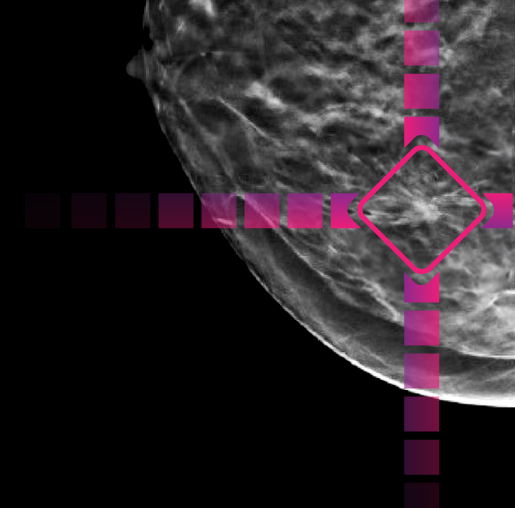

After your exam, Artificial Intelligence (AI) technology2 is applied to your mammogram.

The AI points out areas of interest on your exam to help the radiologist detect very subtle abnormalities.